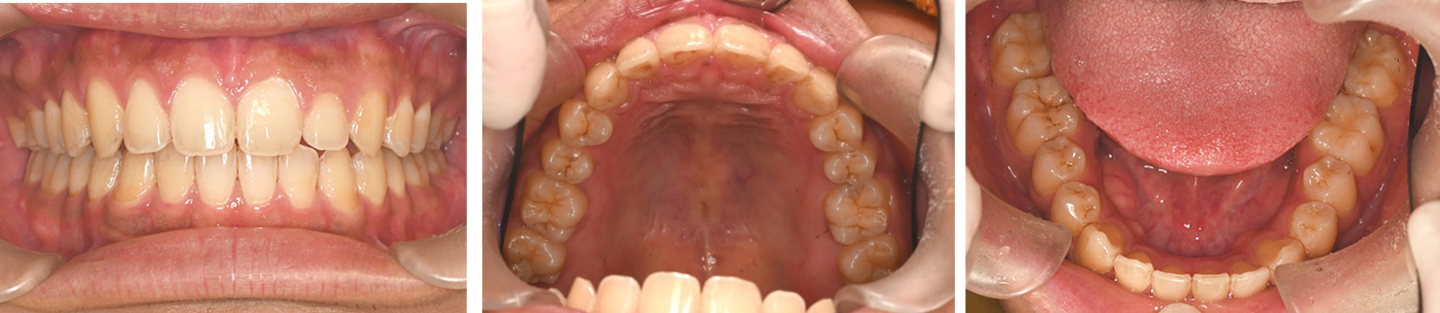

17歳男性 歯列不正 上下抜歯

治療前の写真

治療前

治療後の写真

治療後